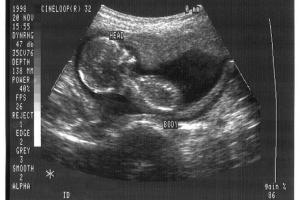

Health researchers need alternatives to using fetal tissue, Department of Health and Human Services leaders have said after several years of controversy and investigations into whether fetal tissue procured from aborted babies was sold illegally.